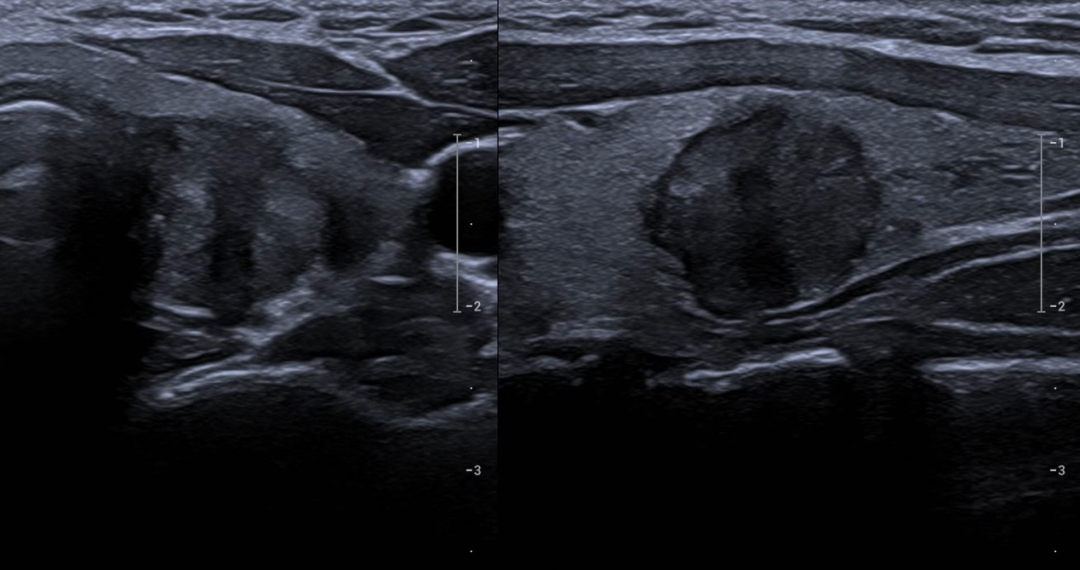

患者的甲状腺乳头状癌结节位于左侧叶,贴近内侧包膜且临近气管,手术风险相对较高。

在此次手术中,罗教授凭借其深厚的专业技术和丰富的临床经验,为患者精准注射隔离液,确保重要结构的安全保护。通过超声实时引导,罗教授采用"移动射击"技术,确保消融范围完全覆盖病灶并留有足够的安全边界。

术后超声造影检查显示,患者的甲状腺结节血供完全阻断,消融效果良好。这一结果与国际研究报告的数据高度一致,证明了微波消融术在甲状腺癌治疗中的可靠性和有效性。